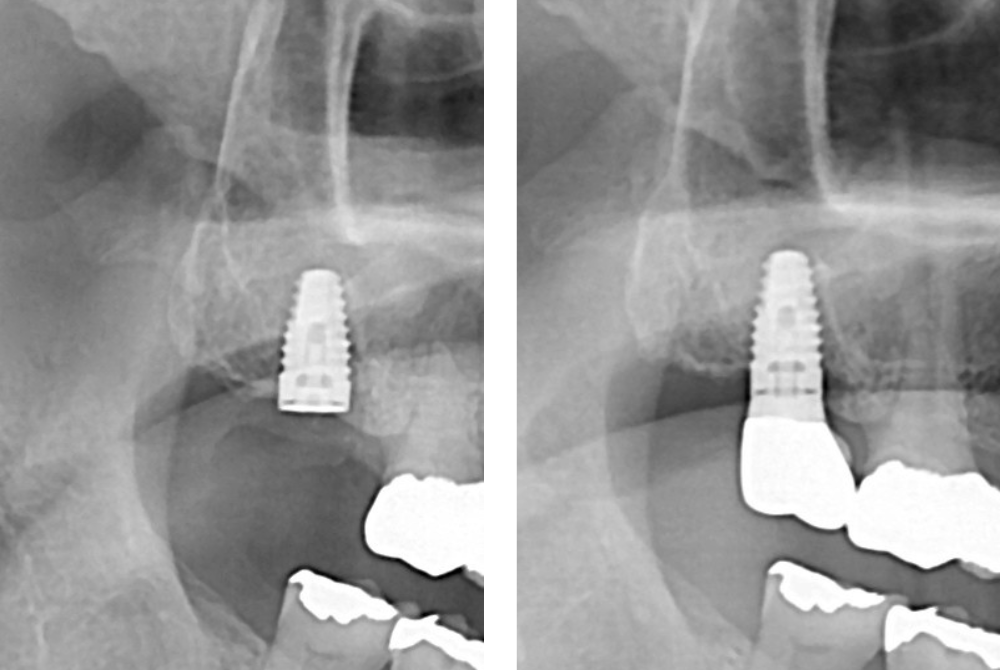

治療後

| 治療内容 | ・患者の症状:歯根破折により抜歯済みの歯にインプラントを埋入 ・治療方法 :CT及びパントモレントゲンからインプラントの埋入位置を計測。麻酔下にてインプラント植立。仮歯を入れて5か月待機。セレック治療にてジルコニアクラウンを製作、同日装着。 ・治療結果 :噛める歯が増えて、噛みやすくなる。 |